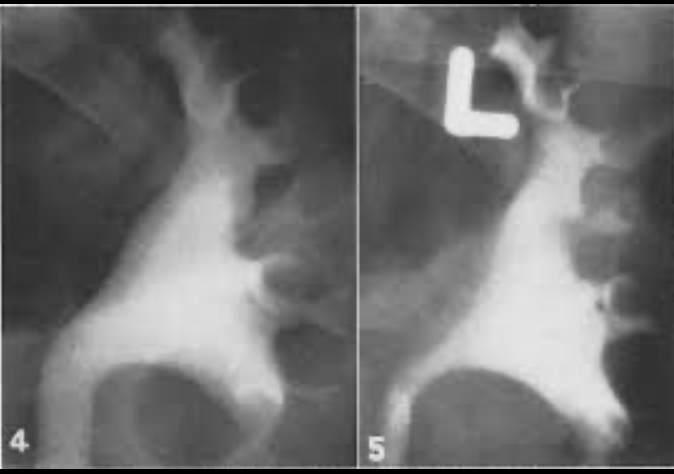

Cerebral palsy patient with blunt abdominal trauma and haematuria.

Postvoid film shows a flame-shaped density adjacent to lateral walls of bladder representing extra-peritoneal contrast from a bladder rupture.

Case courtesy of Dr Ali Nourian, Radiopaedia.org, rID: 27806

Name the radiologic findings of extraperitoneal bladder rupture in VCUG?

A:

1- Pear-shaped bladder

2- Flame-shaped contrast extravasation into perivesical fat best seen on postvoid films

3- Paralytic ileus